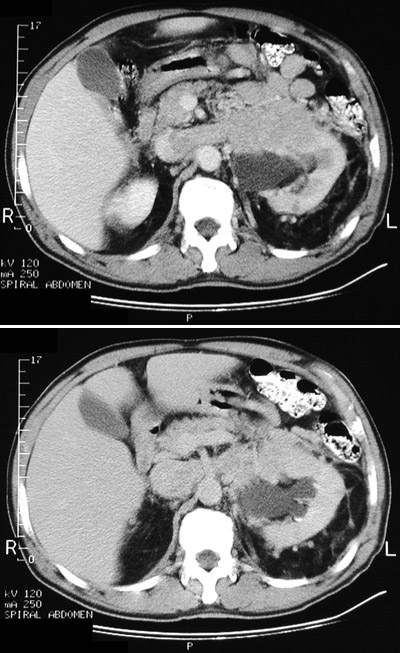

![]() | A renal cell carcinoma is seen here to be invading the left renal vein, distending the vein, and extending into the inferior vena cava. Renal cell carcinomas are known to exhibit this phenomenon. In the lower panel (at a slightly higher level in the body) the renal vein crowds the superior mesenteric artery. |